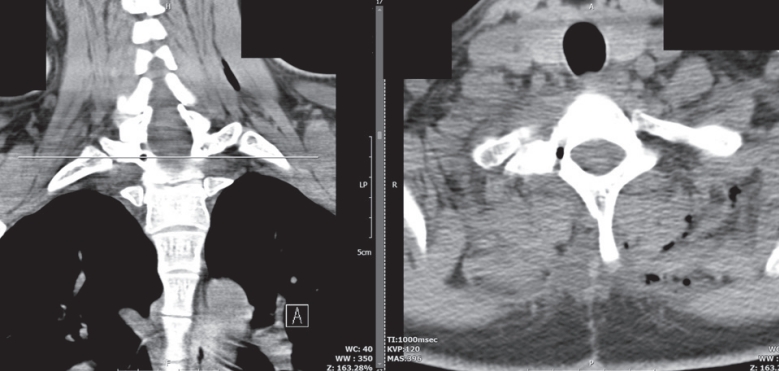

Fig. 1). Given the deep anatomical location, adjacent to both the spinal canal and the vertebral artery, wide laminectomy or facetectomy was deemed excessively invasive and potentially morbid. After a multidisciplinary team discussion, the surgical plan involved targeted resection using intraoperative O-arm–based 3D navigation to maximize precision and minimize exposure. Under general anesthesia, the patient was placed in a prone position. A midline posterior cervical incision was made, and subperiosteal dissection was carried out to expose the posterior elements of C7 and T1 on the right side. Intraoperative O-arm 3D imaging was obtained and registered with preoperative CT and MRI data using a StealthStation

TM navigation platform (Medtronic Inc., USA). The lesion was accurately localized at the junction between the superior pedicular cortex and the transverse process of T1, just inferior to the transverse foramen (

Fig. 2). Using the navigation pointer, the surgical entry point was planned to avoid disruption of the vertebral artery and facet complex. A high-speed diamond burr was used under microscopic magnification to perform a cortical window. The nidus was identified as a red-brown, well-circumscribed lesion with minimal surrounding bleeding. Complete en bloc resection of the nidus was achieved using curettes and a Kerrison punch. Care was taken to avoid injury to the transverse foramen, and no neural structures were exposed or manipulated during the procedure. Histopathological examination of the excised specimen revealed a well-vascularized nidus composed of woven bone trabeculae rimmed by active osteoblasts, consistent with osteoid osteoma. There was no evidence of malignancy. The patient experienced complete resolution of pain on the first postoperative night. No neurological complications occurred. He was mobilized without restriction on postoperative day 1 and discharged on day 2. At 6-week follow-up, he remained pain-free, had resumed full physical activity, and reported significant improvement in sleep quality. At the 6-month follow-up, repeat MRI and CT showed no evidence of recurrence or residual lesion (

Fig. 2.Intraoperative O-arm–based navigation image demonstrating real-time localization of the nidus during surgery. The navigation pointer is positioned over the superior cortex of the right T1 pedicle.